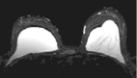

Left images show intracapsular rupture in the left implant ("linguini sign").   Right images from a contrast dynamic scan show an intensely enhancing mass adjacent to a right implant.

MRI is utilized in patients with dense breasts and indeterminate masses who have a non-diagnostic x-ray mammogram and ultrasound.   MRI is only an adjunct technique.   If a mass is suspected, a contrast-enhanced dynamic study is performed with IV Gadolinium.   This is usually done with high-resolution (1-2 mm) coronal sections pre and post rapid infusion of contrast (using an MR-compatible power injector) in a dynamic fashion (usually 4 or 5 post contrast sequences are obtained as shown in top right 3 images).   Contrast uptake graphs of suspicious masses are obtained.   Malignancies tend to take up contrast more rapidly.